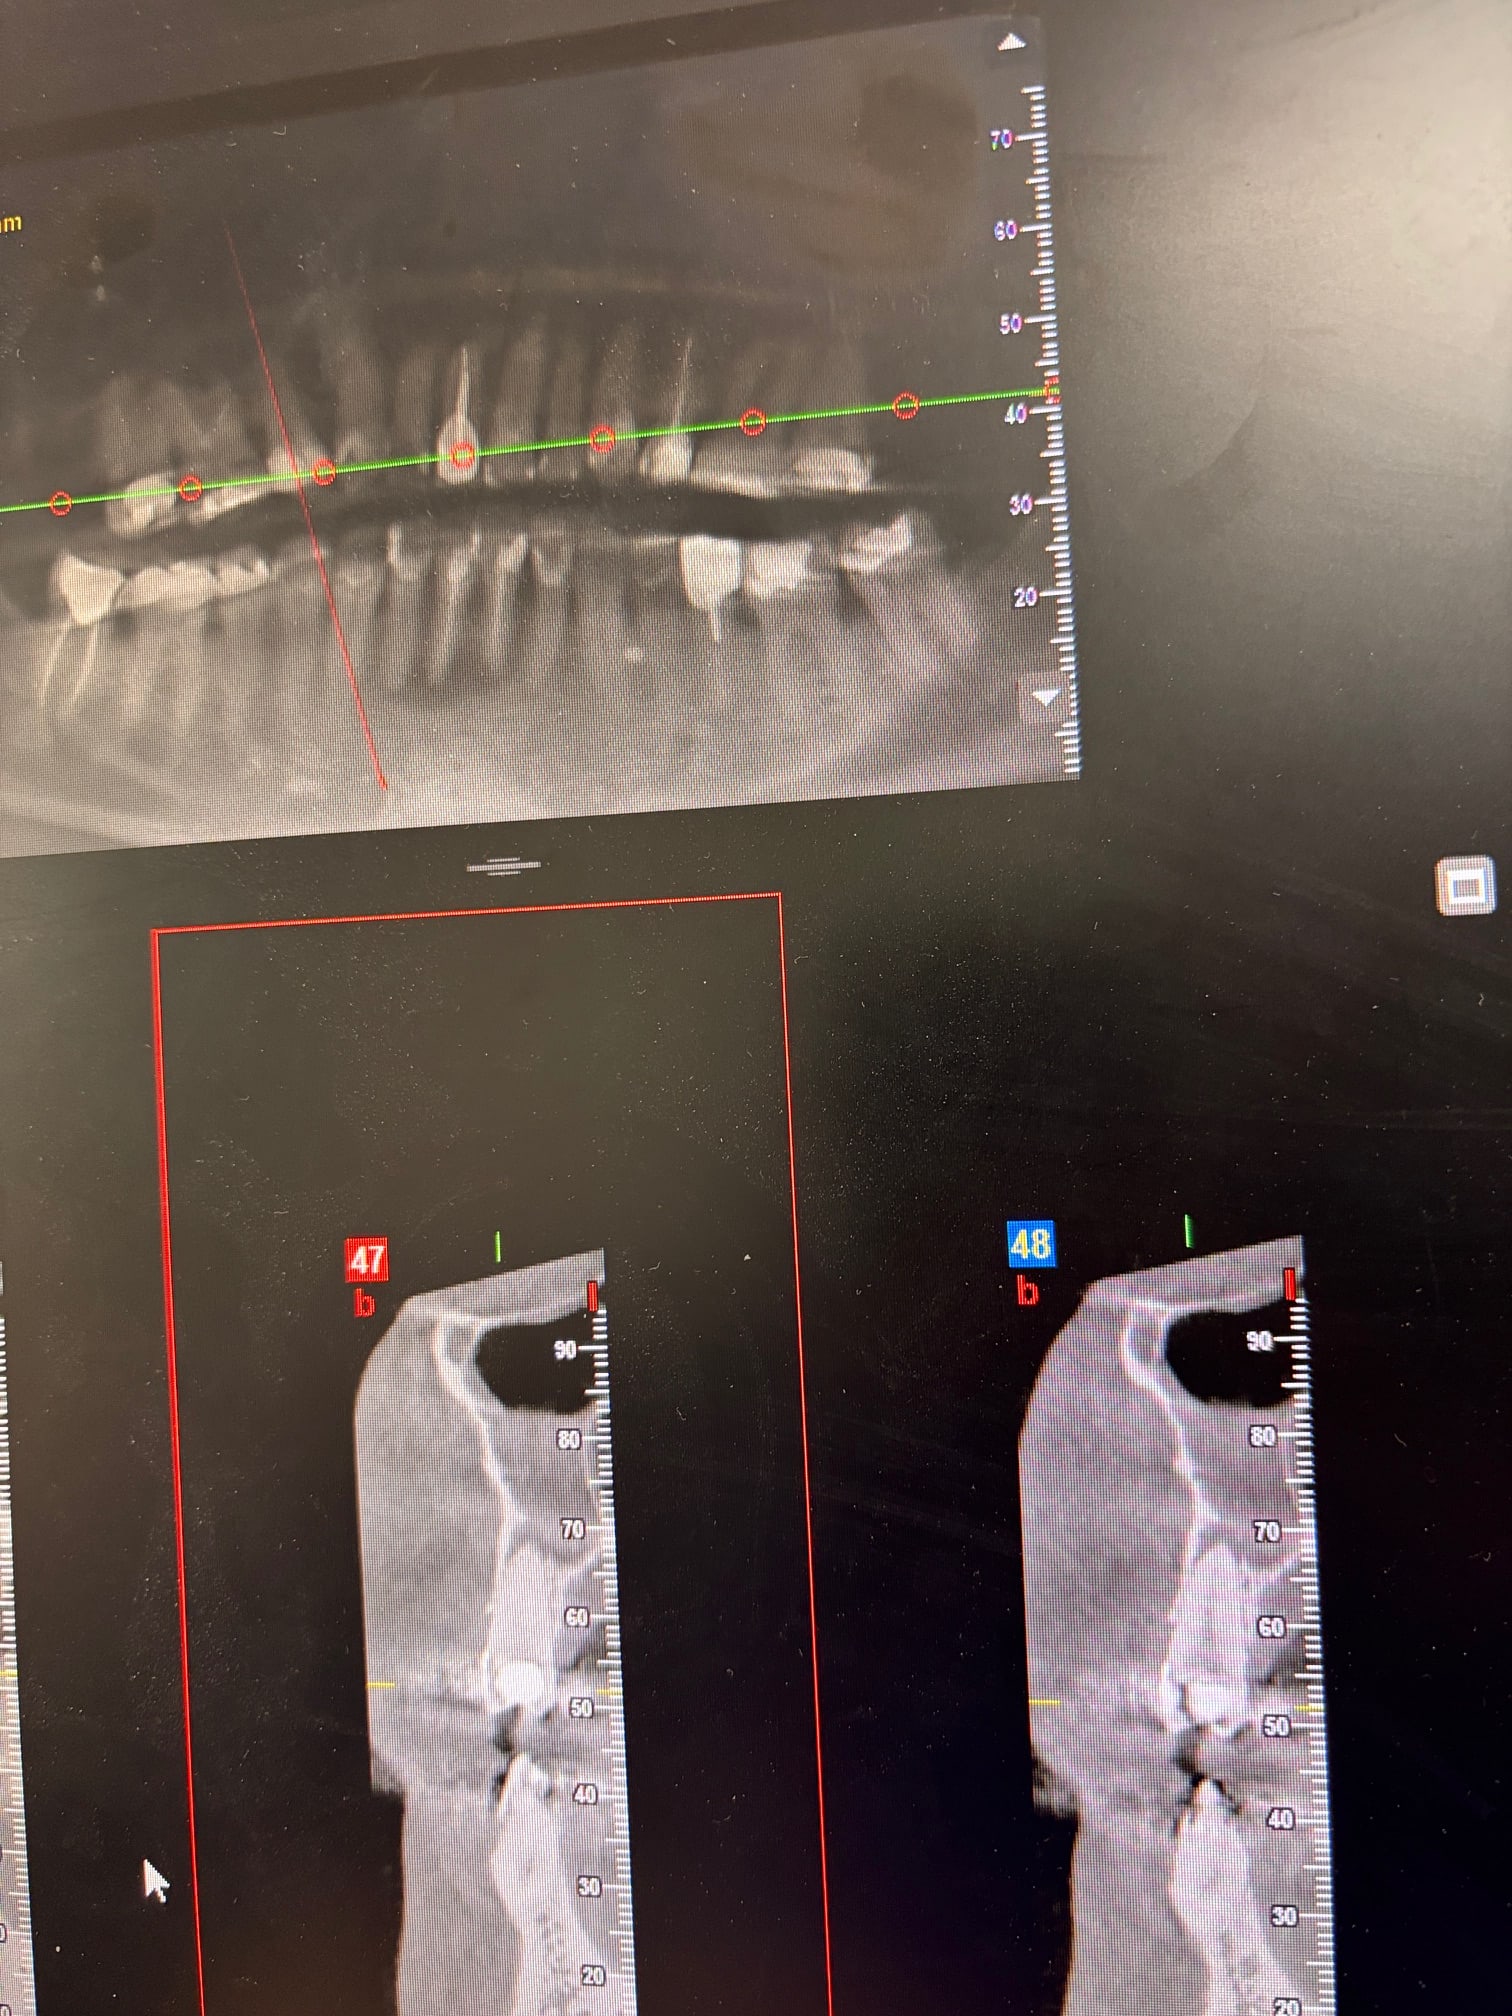

En revanche, rien à voir, mais pourquoi un cbct grand champ avant consentement aux soins pour un des sextants visibles sur une rétro ; là par exemple, sextant 7, quand tu vois à l examen clinique des dents qui ont cette gueule, t'es quasi sûr de voir des LIPOE sur la rétro, perso je fais déjà une proposition de traitement pour ça, puis si le patient accepte on regarde le reste.

Parce que si ton patient refuse ta pdt, il aura été irradié pour rien.

Ben je fais juste mon taf sans me poser de question. Ca a commencé par des rétros avec des images moyennasses . Puis de fil en aiguille, le patient me décrit des épisodes de sinusites assez fréquents.

Vu qu’il y avait des images aux 4 coins, le CB permet de tout vérifier. Et si mon patient ne fait rien, c’est pas mon soucis. Il part avec son cone beam et moi je rentre chez moi en ayant la sensation d’avoir fait mon job. À savoir: examen clinique et radio, entretien avec le patient puis présentation du diag et du plan de traitement. La suite est entre ses mains, pas entre les miennes.